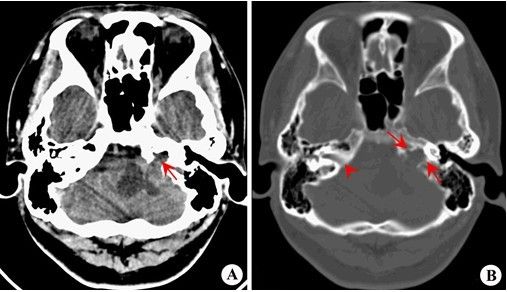

图3. 内听道ct.

ct,注意内听道扩大.

骨窗显示内听道扩大.

内听道喇叭口状扩大---听神经瘤.